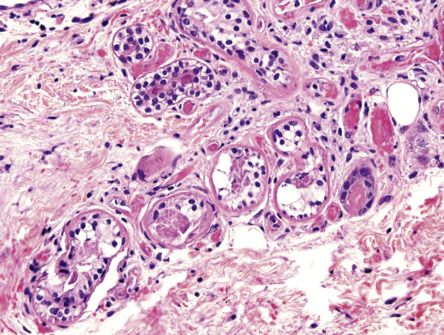

Pathology

The blisters are predominantly subepidermal. However, intraepidermal blisters are also observed as the result of re-epithelialization of older lesions or epidermal spongiosis. There is a variable degree of epidermal necrosis. Sweat gland necrosis is a characteristic finding ( Fig. 33.4 ), and focal necrosis of the epithelium of the pilosebaceous follicles can also be seen. There is only a sparse inflammatory cell infiltrate. DIF is usually negative, but deposits of IgG, IgM and/or C3 have been found within the walls of dermal blood vessels .